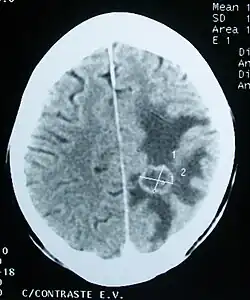

Brain tumors, when compared to tumors in other areas of the body, pose a challenge for diagnosis. Commonly, radioactive tracers are uptaken in large volumes in tumors due to the high activity of tumor cells, allowing for radioactive imaging of the tumor. However, most of the brain is separated from the blood by the blood–brain barrier (BBB), a membrane that exerts a strict control over what substances are allowed to pass into the brain. Therefore, many tracers that may reach tumors in other areas of the body easily would be unable to reach brain tumors until there was a disruption of the BBB by the tumor. Disruption of the BBB is well imaged via MRI or CT scan, and is therefore regarded as the main diagnostic indicator for malignant gliomas, meningiomas, and brain metastases.[41]

Imaging

Medical imaging plays a central role in the diagnosis of brain tumors. Early imaging methods – invasive and sometimes dangerous – such as pneumoencephalography and cerebral angiography have been replaced by non-invasive, high-resolution techniques, especially magnetic resonance imaging (MRI) and computed tomography (CT) scans.[42] MRI with contrast enhancement is the preferred imaging test in the diagnosis of brain tumors.[24][43] Glioblastomas usually enhance with contrast on T1 MRI weighted MRI imaging, and on T2 with FLAIR imaging showing hyperintense cerebral edema.[24] Low grade gliomas are usually hypointense on T1 MRI, and hyperintense with T2 with FLAIR MRI. Meningiomas are usually homogenously enhanced with dural thickening on MRI.[24]

Computed Tomography (CT) Scan – uses x-rays to take pictures from different angles and computer processing to combine the pictures into a 3D image. A CT scan usually serves as an alternative to MRI in cases where the patient cannot have an MRI due to claustrophobia or pacemaker. Compared to MRI, a CT scan shows a more detailed image of the bone structures near the tumor and can be used to measure the tumor's size.[51] Like an MRI, a contrast dye may also be injected into the veins or ingested by mouth before a CT scan to better outline any tumors that may be present. CT scans use contrast materials that are iodine-based and barium sulfate compounds. The downside of using CT scans as opposed to MRI is that some brain tumors do not show up well on CT scans because some intra-axial masses are faint and resemble normal brain tissue. In some scenarios, brain tumors in CT scans may be mistaken for infarction, infection, and demyelination. To suspect that an intra-axial mass is a brain tumor instead of other possibilities, there must be unexplained calcifications in the brain, preservation of the cortex, and disproportionate mass effect.[52]